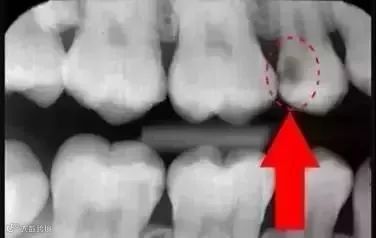

先放几张图,让你们涨涨姿势

不拍片根本不知道你的牙齿长得会有多奇葩!

从下图中可以知道除了外层的一点牙釉质

牙齿里面出了问题,肉眼是无法观察到的

牙医不长透视眼

当然不能透过现象看到牙齿本质喽

圈出来的地方或多或少都有点龋齿

▼

但是有些你并不能看见

这些龋齿还浅不会让你有什么感觉

顶多吃东西塞牙,和冷水敏感而已

暗的部位说明龋齿已经非常严重了!